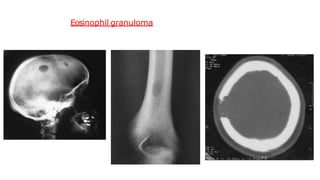

Eosinophil granuloma

🠶 Isthe mildest and most frequent form of Langerhans

histiocytosis.

🠶 It occurs in children and young adults

🠶 Lytic lesions which may be single or multiple, most frequently in

the skull, pelvis, femur and ribs.

🠶 May have the features of an aggressive lesion, or well defined

and may have a sclerotic rim.

🠶A periosteal reaction issometimes seen.